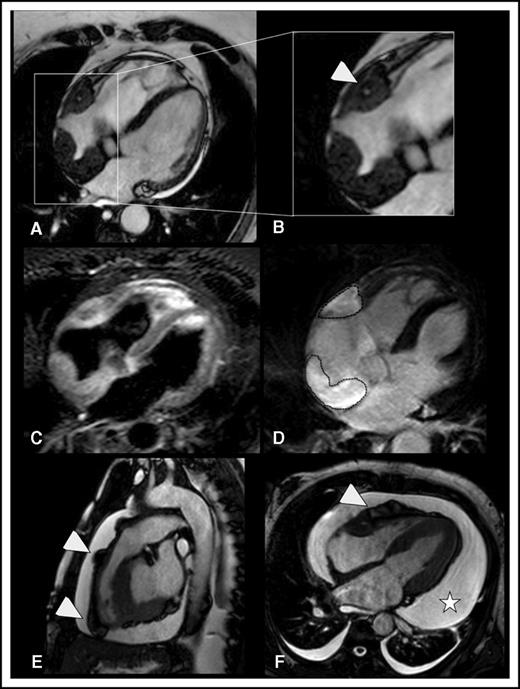

Myocardial and pericardial involvement in ECD. (A-D) Myocardial lesions. ECD typically affects the myocardium by infiltrating the posterior wall of the right atrium, forming soft tissue density masses with smooth surface, which appear hypointense in b-SSFP sequences (the lesions are framed in A). This b-SSFP hypointense infiltration also develops in the right atrioventricular groove, where it encases the right coronary artery (arrowhead in B). T2w image with signal fat suppression shows that there might be diffuse slight hyperintensity within the soft tissue, which usually corresponds to edema (C). In inversion recovery T1w sequences, late enhancement of the lesional soft tissue likely reflects disease activity/inflammation (dotted lines in D). (E-F) Pericardial lesions. ECD-related infiltration of the pericardium causes soft tissue density nodules arising from the visceral pericardial sheets, in association with pericardial effusion. b-SSFP sequences (E-F) allow optimal visualization of the nodules that appear hypointense as compared with the hyperintense pericardial effusion. Arrowheads indicate soft tissue pericardial nodules in the right ventricle outflow tract (E) and right ventricle free wall (F). The pericardial nodules are associated with conspicuous circumferential pericardial effusion (star in F). (A-D,F) Four-chamber view (a plane that allows comprehensive evaluation of myocardium and pericardium). (E) Sagittal view (the best plane to depict the right ventricle ouflow tract).

Twenty patients (87%) were men; the median age at diagnosis was 48 years (range 22-72). Fourteen patients (61%) had traditional cardiovascular risk factors (eg, diabetes, dyslipidemia), and 5 patients had overt cardiovascular disease (eg, coronary artery disease, peripheral arterial disease, atherosclerotic aortic aneurysm) prior to ECD diagnosis (supplemental Table 1, available on the Blood Web site). Table 1 illustrates the main sites involved by the disease. Ten patients (43%) had MRI evidence of cardiac involvement, with myocardial involvement in 9 and pericardial involvement in 9. Six patients had thoracic large-vessel involvement together with cardiac lesions, whereas only 1 patient had thoracic aorta involvement without cardiac disease (Table 1). MRI revealed peculiar patterns of myocardial involvement (Figure 1): most patients with cardiac disease had right atrial involvement, usually in the form of an atrial pseudotumoral mass, mainly involving the posterior atrial wall and often protruding into the atrium; another common lesion was the infiltration of the right atrioventricular sulcus, where the tissue usually surrounded or infiltrated the right coronary artery. However, none of the 7 patients with right pericoronary infiltration had ECD-related ischemic cardiac lesions. Unlike other infiltrative disorders, ECD did not cause diffuse infiltration of the myocardium, a finding in line with the usually normal systolic or diastolic functions observed by MRI or echocardiography (Table 1; supplemental Table 1; supplemental Video 1). Pericardial infiltration/thickening was common, often accompanied by pericardial effusion (Figure 1; supplemental Video 1) leading to tamponade in 2 cases and requiring pericardiocentesis in 3 cases. Unlike in other reports,2 we found no MRI evidence of ECD-related valvular disease. Thoracic large-artery involvement was generally characterized by perivascular thickening of the thoracic aorta and the origin of the epiaortic arteries (supplemental Figure 1), but no luminal narrowing or aneurysms were detected.